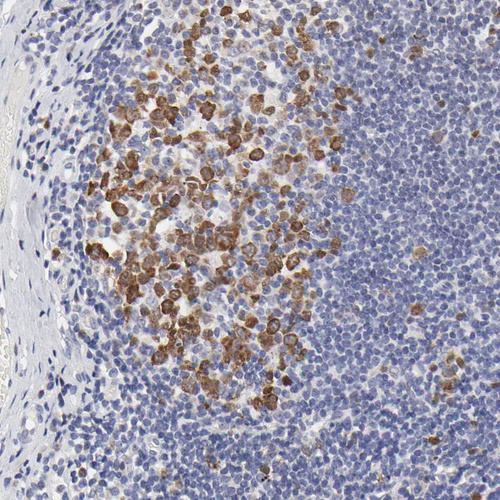

Immunohistochemistry analysis in human testis and kidney tissues using HPA002647 antibody. Corresponding NCAPH RNA-seq data are presented for the same tissues.